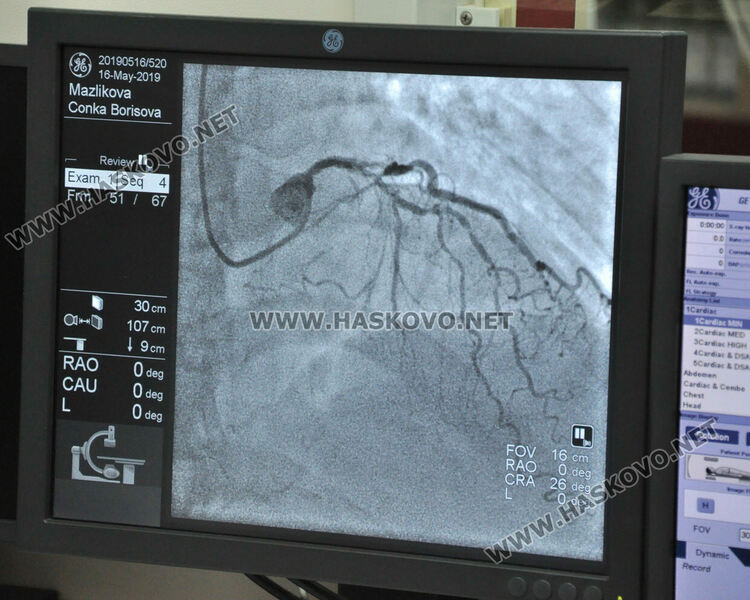

Според последните данни на Районната здравноосигурителна каса (РЗОК) в Хасково 58 477 души в областта са диспансерни със заболявания на сърдечно-съдовата система. Само за месец януари тази година здравната каса е заплатила медикаменти за лечението им на стойност 537 300 лева. Доплащането от страна на болните с такива диагнози е било близо 58 000 лв.

„Пациентът има ангажимент да доплати за своя сметка определена сума. Процентите, с които финансира осигурителната институция, могат да бъдат 25%, 50%, 75% и 100% от стойността на лекарствата. Към момента в позитивния лекарствен списък има активни 1139 лекарства, които касаят лечение на сърдечно- съдови проблеми. 346 от тях са 100% финансирани от страна на НЗОК, обясни директорът на  РЗОК Ирина Колева.

Очаква сърдечно болните да намалят още повече разходите си за медикаменти. Това ще стане след като касата плати повече за лекарствени продукти от 52 групи, предназначени за лечение на хронични заболявания на сърдечно-съдовата система. Към списъка ще се прибавят и  още 56 медикамента, които ще бъдат напълно безплатни.